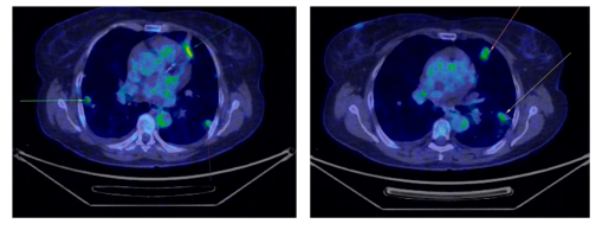

术后5个月PET-CT显示双肺多发非钙化小结节,代谢轻度增高,提示转移(图1)。

图1 首次PET-CT显示双肺多发非钙化性结节(以黄色和绿色圆圈标出)

术后6个月PET-CT示肺结节

数量、大小及代谢均进一步增加,最大约 28 × 20 mm(图2)。穿刺活检:PAX8(+)、CD10(+)、CK7(–)、S100(–)、Ki-67 15–20%。

图2 第二次PET-CT扫描显示肺部病灶进展(以箭头标示)